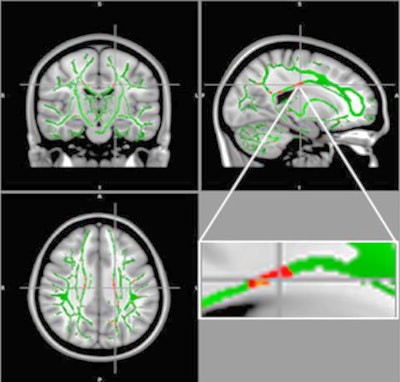

Obesity causes a myriad of adverse effects, including inflammation in the nervous system that could damage key brain regions. One approach to gauge the severity of damage is through DTI, an MRI technique that measures the flow of water molecules in the brain's white matter through fractional anisotropy. Reductions in fractional anisotropy are indications of poor white-matter integrity.

The DTI results showed a reduction of fractional anisotropy values in the obese adolescents in regions located in the corpus callosum, which connects the left and right hemispheres of the brain. The researchers also observed a decrease of fractional anisotropy in the middle orbitofrontal gyrus, which is associated with the control of emotions and the brain's response to rewards. Interestingly, they found no brain regions with an increase in fractional anisotropy in the obese patients.